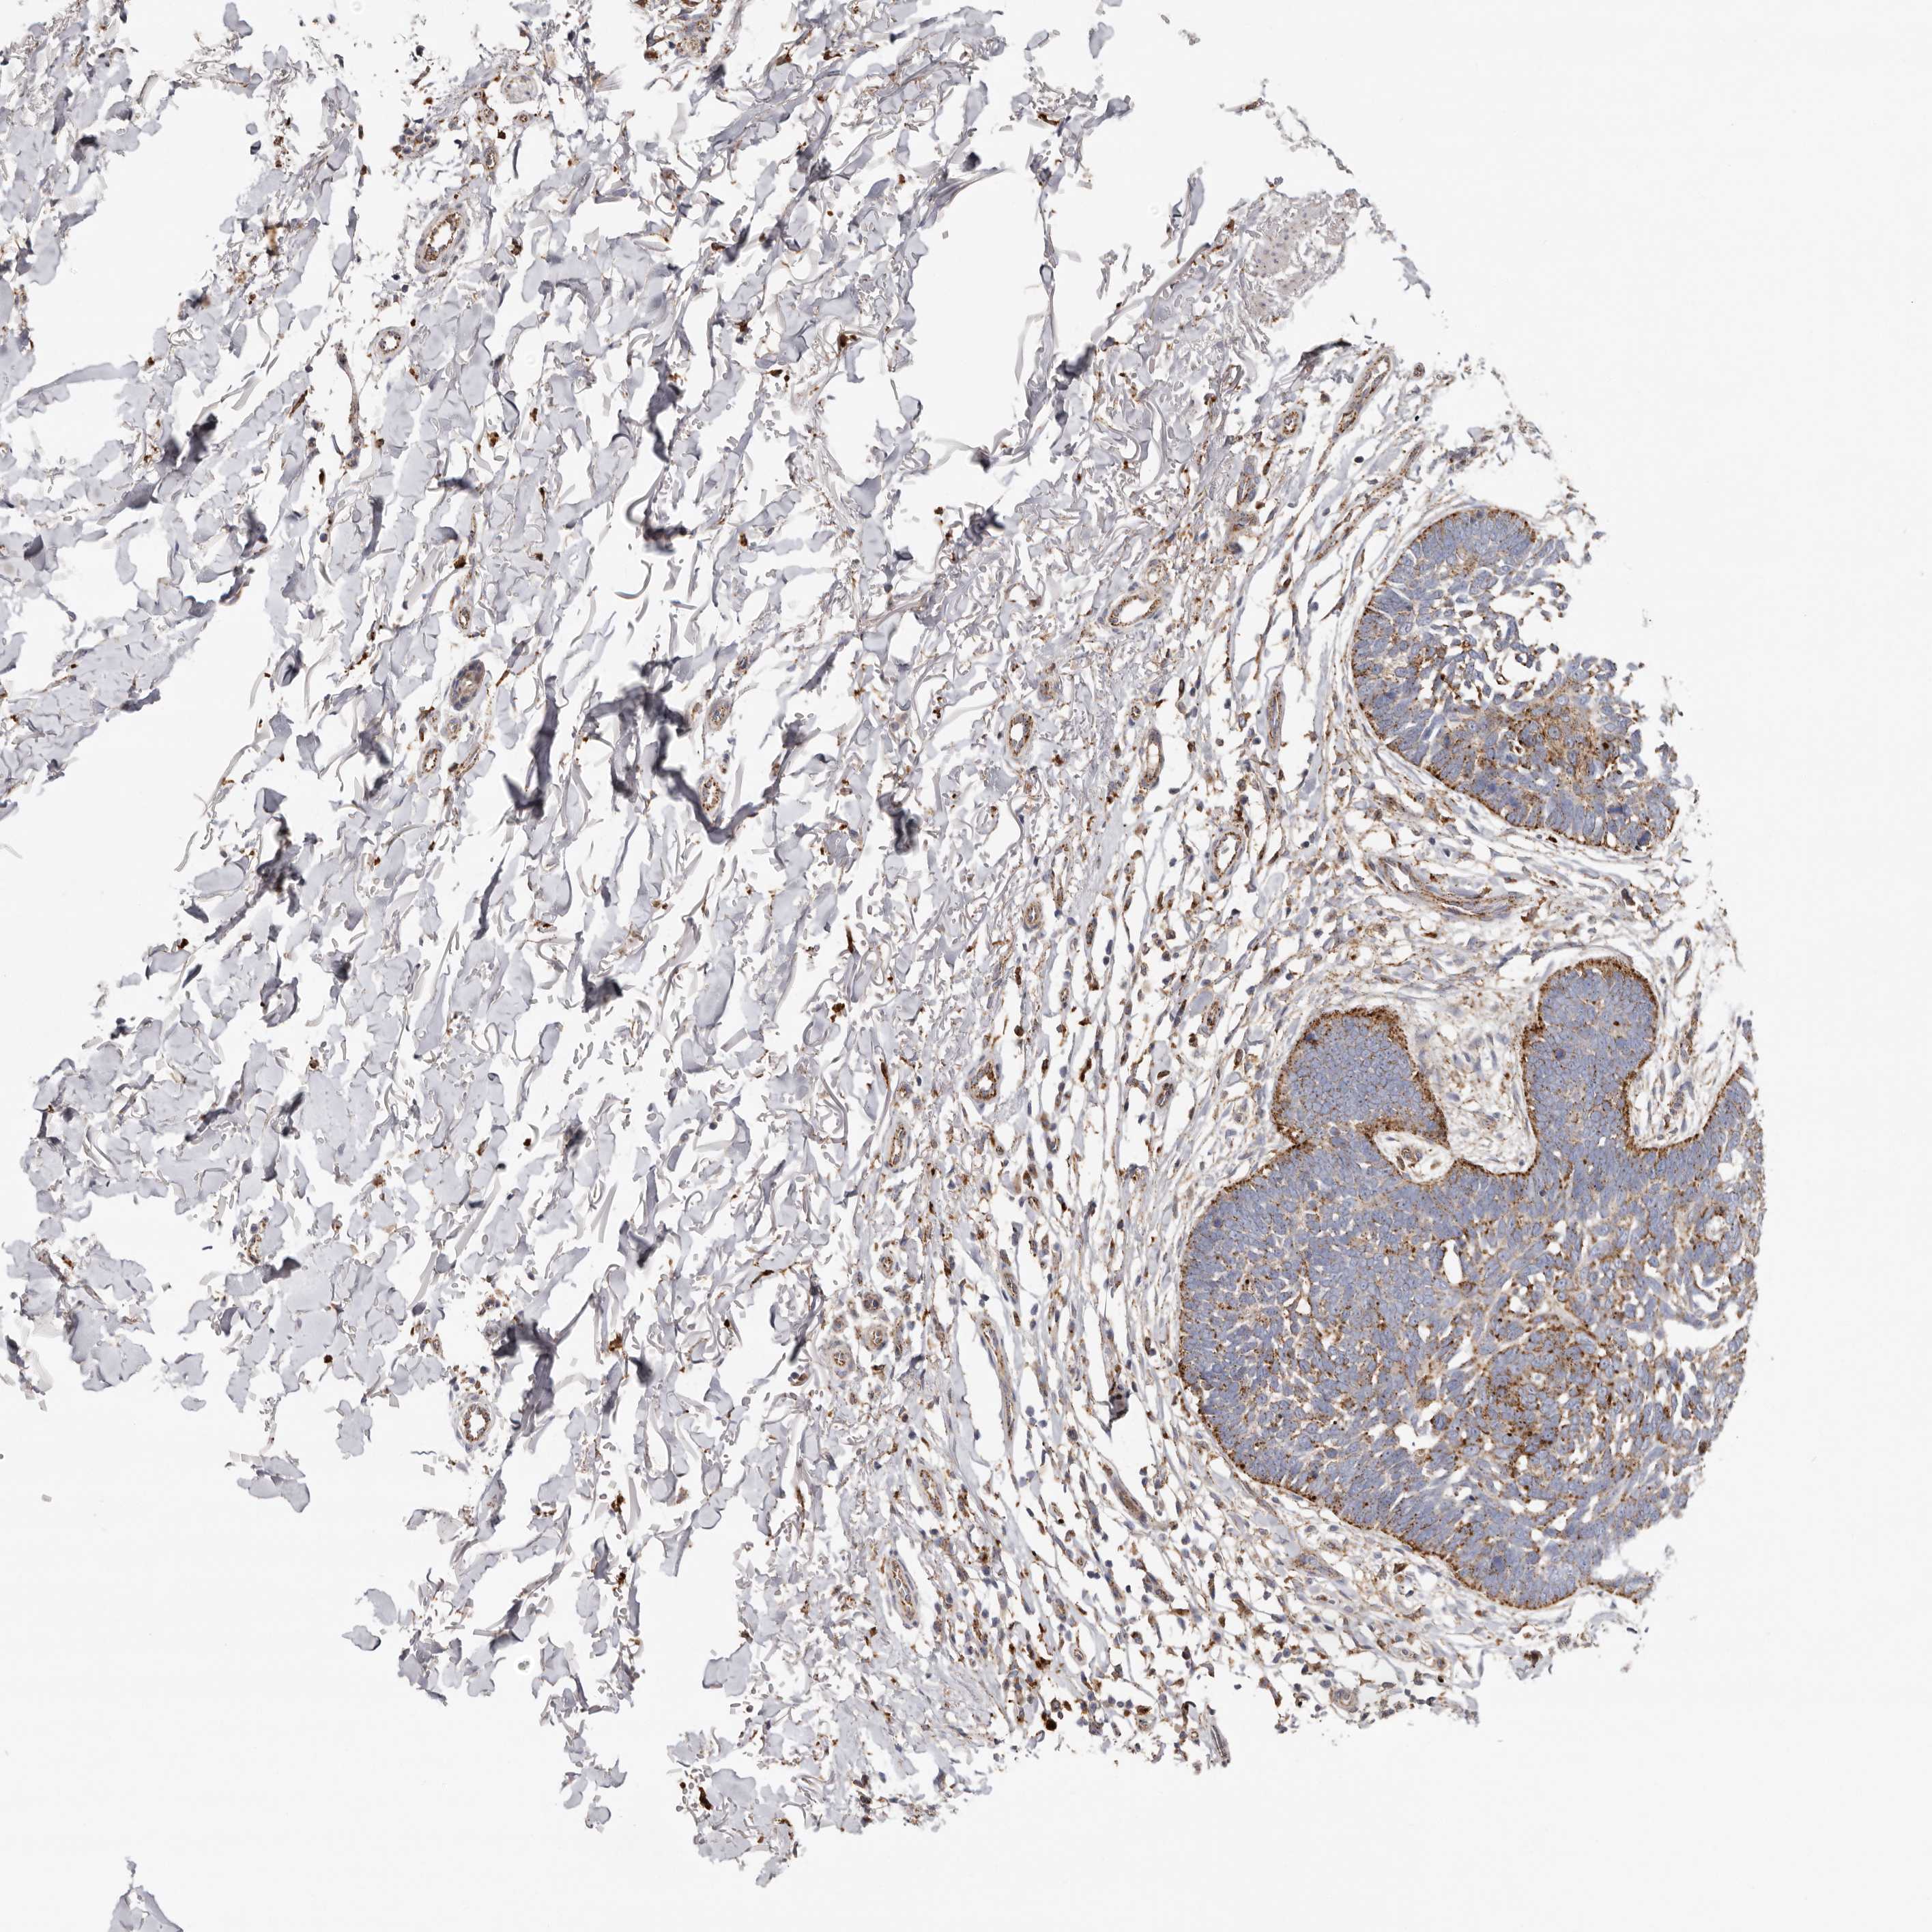

SKIN CANCER - Protein expressioni

A mouse-over function shows sample information and annotation data. Click on an image to view it in a full screen mode. Samples can be filtered based on level of antibody staining by selecting one or several of the following categories: high, medium, low and not detected. The assay and annotation is described here.

Antibody stainingi

Antibody staining in the annotated cell types in the current human tissue is reported as not detected, low, medium, or high, based on conventional immunohistochemistry profiling in selected tissues. This score is based on the combination of the staining intensity and fraction of stained cells.

Each image is clickable and will lead to virtual microscopy that enables deeper exploration of all samples and also displays staining intensity scores, fraction scores and subcellular localization as well as patient and tissue information for each sample.

Antibody HPA028747

Squamous cell carcinoma, metastatic, NOS